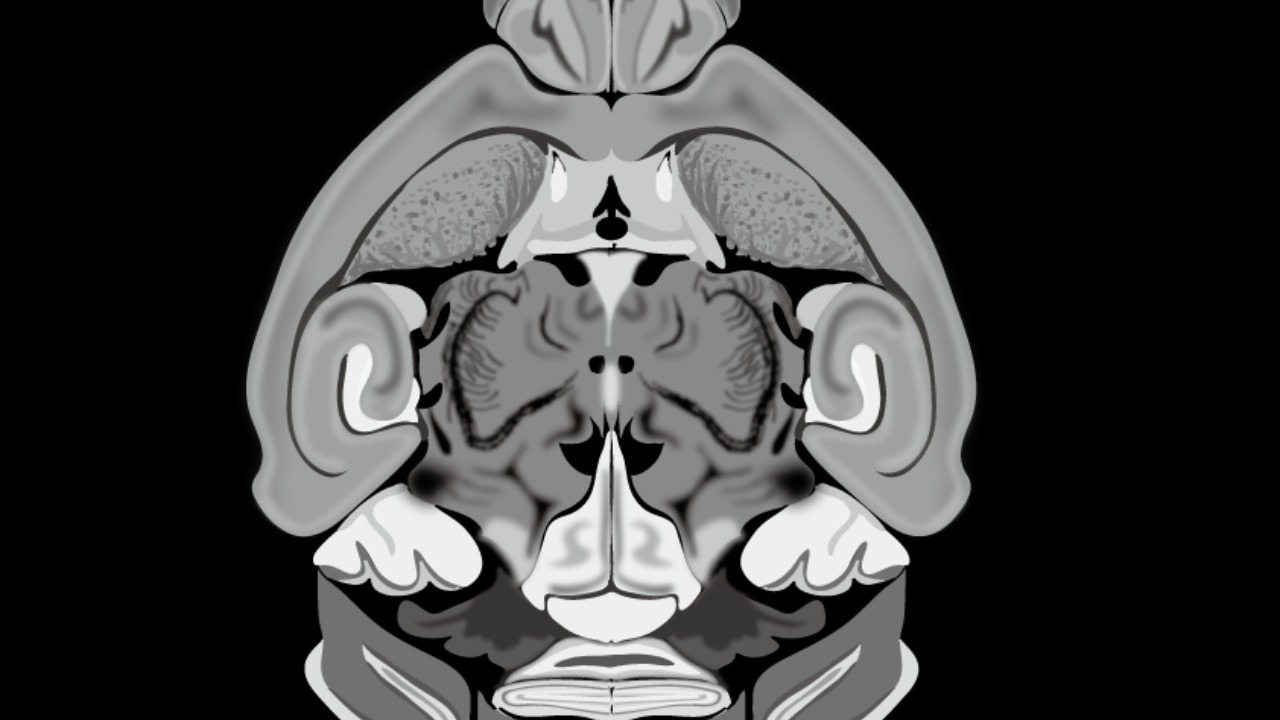

Scientists at Harvard University and Google have achieved a groundbreaking milestone by utilizing artificial intelligence to create the first comprehensive map of a cubic millimeter of mouse brain tissue. This effort uncovered previously uncharted neural connections in the mesopontine tegmentum, a region involved in arousal and locomotion. As part of the BRAIN Initiative launched in 2013, the project involved analyzing over 100,000 neurons and millions of synapses using advanced machine learning algorithms to process vast electron microscopy data (Live Science).

The AI-generated map led to several novel discoveries, including the identification of rare neural cell types and unexpected synaptic connections in the mesopontine tegmentum. These findings could have implications for understanding sleep-wake cycles and other neurological functions (Live Science). Quantitative insights from the study revealed the mapping of 150,000 cells and 200 million synapses within the 1 mm³ volume, indicating a denser neural wiring than previously anticipated (Neuroscience News).

These discoveries hold significant implications for understanding brain disorders. According to lead researcher Lichtman, these detailed maps could inform models of neurological conditions like Parkinson’s disease, potentially leading to new therapeutic strategies and a deeper understanding of these complex disorders (Live Science).